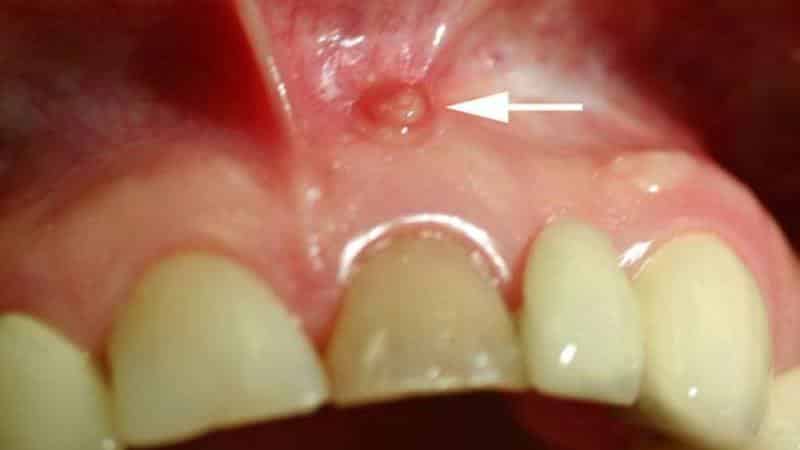

- образование небольшого пузырька в корневой области, который со временем увеличивается и наполняется жидкостью;

- появление флюса или свища.

В более тяжелых случаях кисты в ротовой полости, как показано на фото ниже, легко выявляются при обычном визуальном осмотре. Внешне они выглядят как мешочки значительных размеров, наполненные гнойным содержимым. Обратите внимание на изображение кисты на небе.